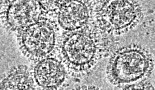

미국 국립보건원(NIH) 연구팀이 인플루엔자 바이러스의 돌연변이에 대항할 수 있는 항체를 발표했다. 보편적인 인플루엔자 백신의 타깃이 아닌 부위를 타깃하는 이 항체는 두가지 바이러스 단백질에 결합한다. 최근의 인플루엔자 백신들은 바이러스 표면에 존재하는 헤마글루티닌(Hemagglutinin, HA)을 타깃하여 바이러스가 숙주 세포에 부착하는 것을 막는 기전을 이용한다. 하지만 이 부위는 백신의 기전을 피하기 위한 돌연변이가 많이 일어난다는 문제가 있다. NIH의 알레르기 및 감염병연구원(NIAID)은 헤마글루티닌을 인식하는 항체가